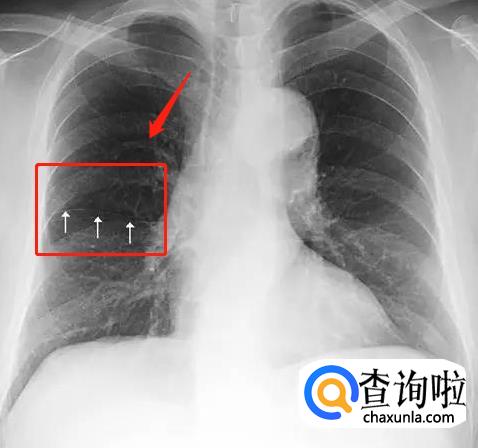

肺纹理。肺动静脉自肺门开始逐级向肺内分支,在胸部X线平片上形成自肺门向肺野外围分布的,逐渐变细的树枝状影像叫肺纹理。正常情况双肺下野肺纹理较肺上野明显,肺野内带肺纹理明显,外带肺纹理很细几乎难以辨认。右肺下野内带不像左肺下野内带那样有心脏的遮挡,故肺纹理尤其明显。